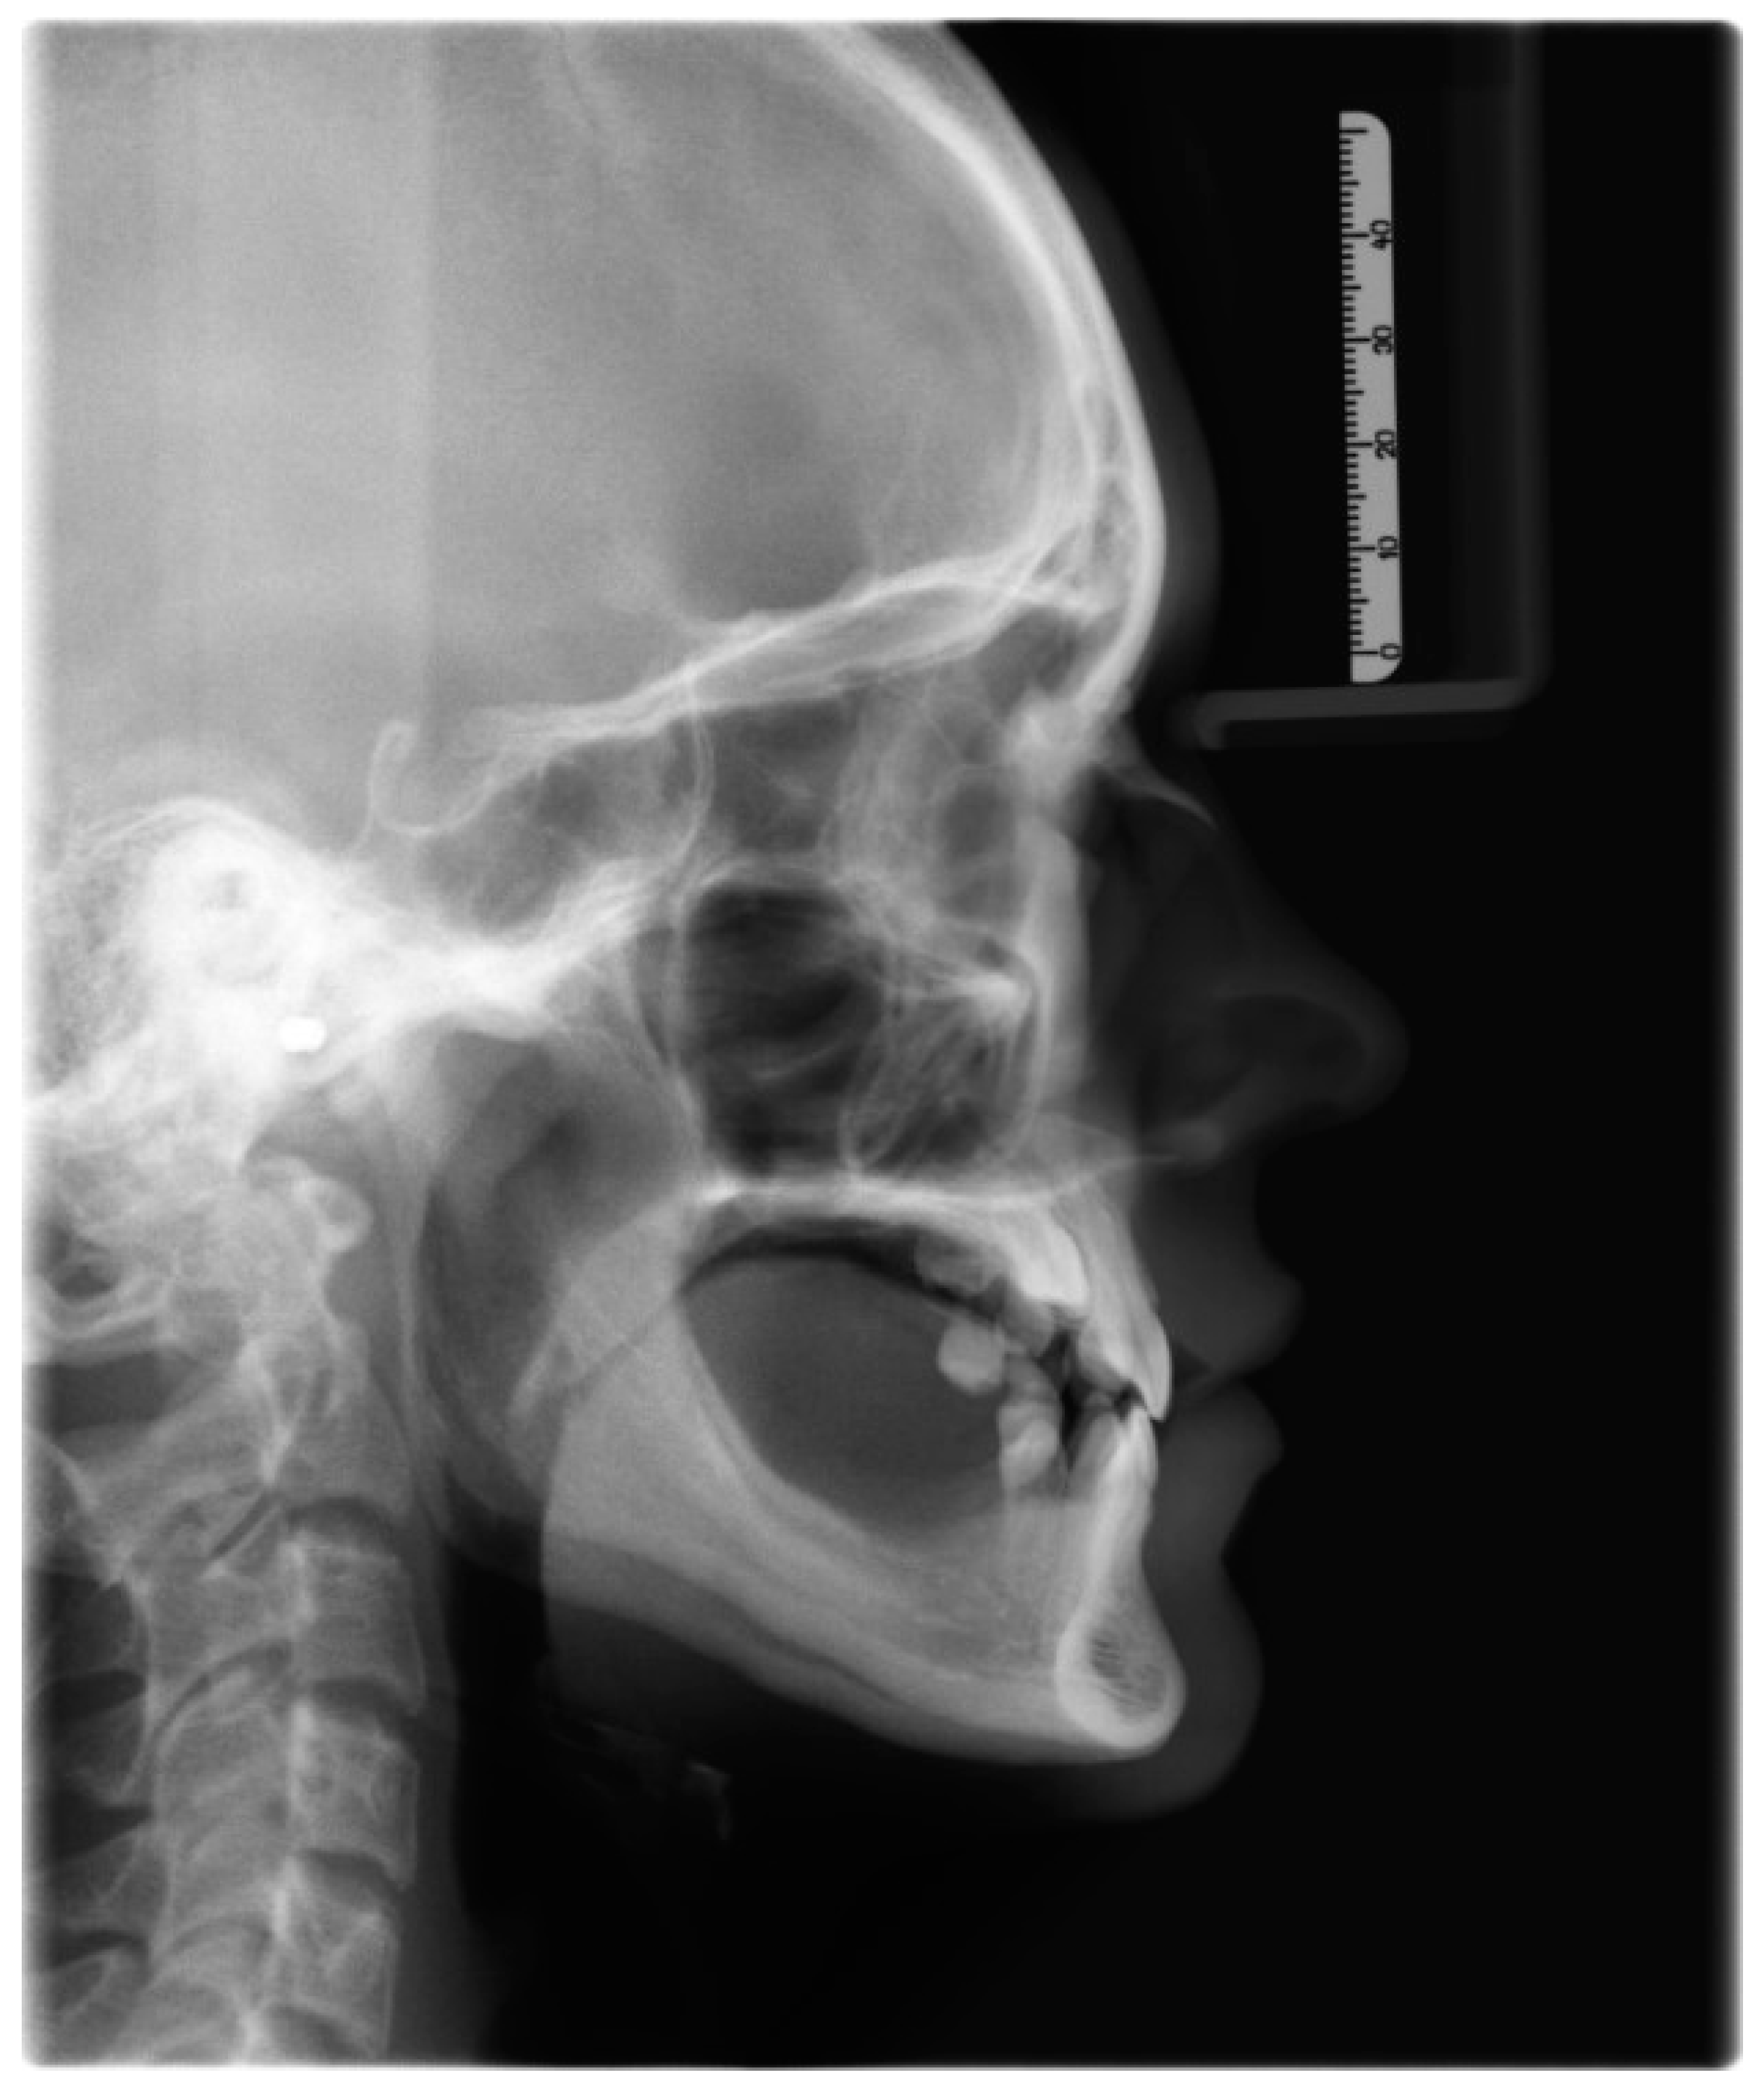

| Measurement | Norm | Deviation | Value |

|---|---|---|---|

| SNA | 82.0° | ± 3.0 | 82.9° |

| SNB | 80.0° | ± 3.0 | 83.6° |

| ANB | 2.0° | ± 2.0 | −0.7° |

| SNPg | 81.0° | ± 3.0 | 86.0° |

| GntgoAR | 122.0° | ± 7.0 | 121.8° |

| NL-NSL | 8.0° | ± 4.0 | 3.1° |

| ML-NSL | 28.0° | ± 5.0 | 26.2° |

| ML-NL | 20.0° | ± 7.0 | 23.1° |

| 1+:NA | 21.0° | ± 4.0 | 17.2° |

| 1+:NA (mm) | 3.7 mm | ± 2.0 | 3.2 mm |

| 1+:NL | 110° | ± 6.0 | 104° |

| 1−:NB | 24.0° | ± 4.0 | 10.5° |

| 1−:NB (mm) | 3.8 mm | ± 2.0 | 0.4 mm |

| 1−:ML | 94° | ± 7.0 | 79.2° |

| 1−:APg | 1.0 mm | ± 2.0 | −1.4 mm |

| 1+:1− | 133.0° | ± 8.0 | 153.5° |

| UL—“E” plane | −4.7 mm | ± 2.0 | −4.35 mm |

| LL—“E” plane | −2.0 mm | ± 2.0 | −4.45 mm |